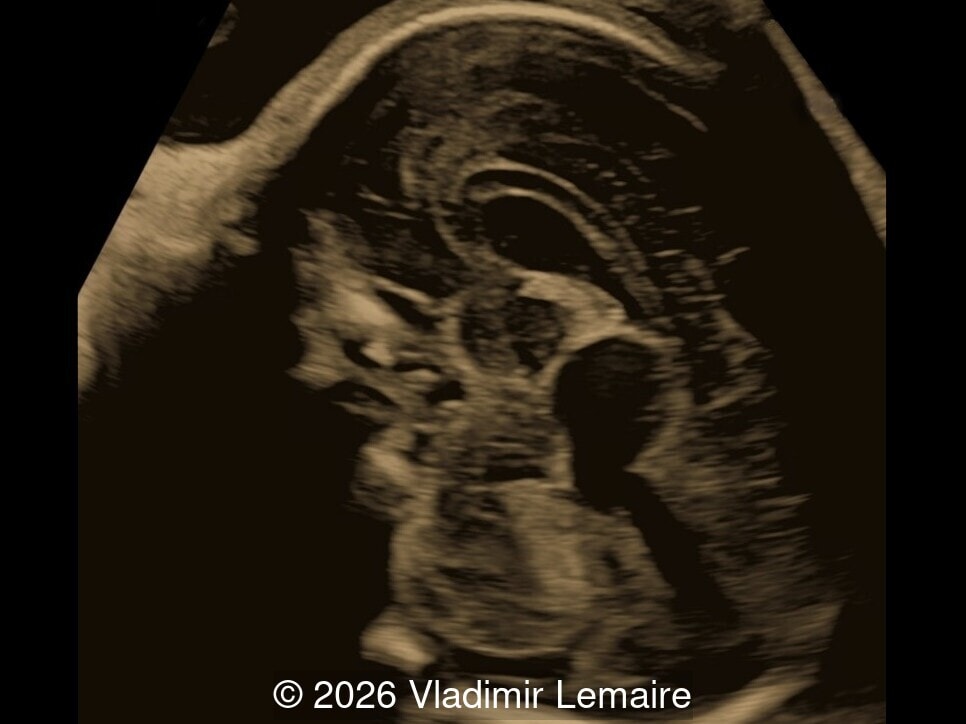

Axial image of the fetal head

Image 7 Axial image of the fetal head